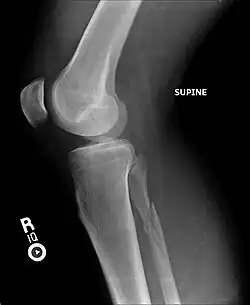

Radiograph showing a Maisonneuve fracture of the proximal fibula